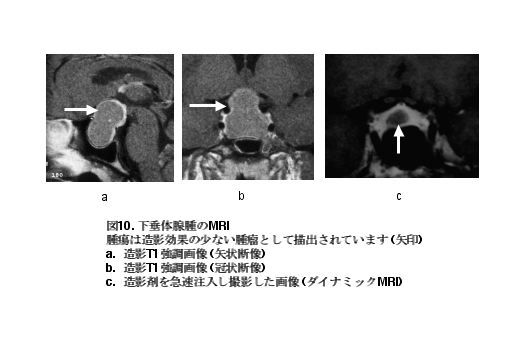

下垂体腺腫の診断は何といってもMRIが有用です。特に造影剤を用いた画像の冠状断像および矢状断像が有用です。下垂体腺腫は造影効果の少ない腫瘍として描出されます (図10a,

10b)。また、腫瘍が小さい場合は、造影剤の急速注入下に時間経過とともにMRIを連続して撮影し (ダイナミックMRI)、確実に診断する方法もあります(図10c)。